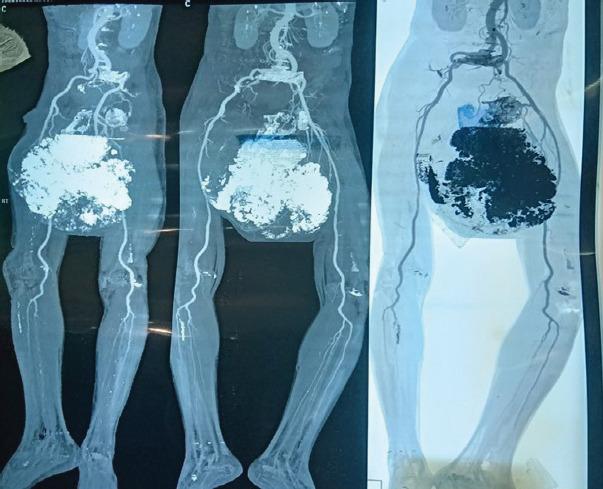

A 60-year-old male presented with a colossal swelling at groin reaching up to distal thigh. He was walking with a wide-based gait due to pain and discomfort. 30 year back, the patient first reported this swelling of pea size, for which he was advised surgery but due to fear of surgery and economic reason he refused. Swelling gradually increased in size and reached up to distal thigh in the past 30 years. It was hard and non-tender up to 6 months back, when suddenly a change in consistency from hard to soft in distal area was noticed. On examination, a large soft cystic swelling was hanging from his pubic area. Tumor was fixed at base on proximal end. On magnetic resonance imaging, size of tumor was 281 mm in length, 263 mm in width, and 250 mm in anteroposterior diameter. Tumor was arising from superior and ischiopubic rami. However, no intra-articular extension was seen. A radiographic skeletal survey and bone scan did not reveal any other lesion. On biopsy, chondrogenic tumor composed of lobules of chondroid material with no cellular atypia or evidence of malignancy was reported. Considering the age of patient, rapid progression in recent months, size and duration of tumor, and type 3 pelvic resection was planned. Using utilitarian pelvic incision with perineal extension, separating long adductor muscles and deep femoral artery tumor, tumor excised with osteotomy at pubic symphysis, and on superior and inferior pubic rami. With minor wound complications, wound healed in 3 weeks. Post-operative biopsy reported as Grade 1 chondrosarcoma. At 3-year follow-up, the patient has no complains and no sign of recurrence noticed.

一名60岁男性,腹股沟处出现巨大肿胀,一直延伸至大腿远端。由于疼痛和不适,他走路时呈宽基步态。30年前,患者首次报告豌豆大小的肿胀,当时建议他手术,但由于害怕手术和经济原因,他拒绝了。在过去30年里,肿胀逐渐增大,直至大腿远端。直到6个月前,肿物一直坚硬且无压痛,之后远端区域突然出现质地从硬变软的变化。检查时,一个巨大的软囊性肿物从耻骨区垂挂下来。肿瘤在近端基部固定。磁共振成像显示,肿瘤长径281毫米,宽径263毫米,前后径250毫米。肿瘤起源于耻骨上支和坐骨耻骨支。然而,未见关节内侵犯。影像学骨骼检查和骨扫描未发现其他病变。活检报告为软骨性肿瘤,由软骨样物质小叶组成,无细胞异型性或恶性证据。考虑到患者年龄、近几个月的快速进展、肿瘤大小和病程,计划行3型骨盆切除术。采用带会阴延长的实用型骨盆切口,分离长收肌和股深动脉,在耻骨联合处以及耻骨上、下支行截骨术切除肿瘤。术后伤口出现轻微并发症,3周后愈合。术后活检报告为1级软骨肉瘤。在3年随访中,患者无不适主诉,未发现复发迹象。